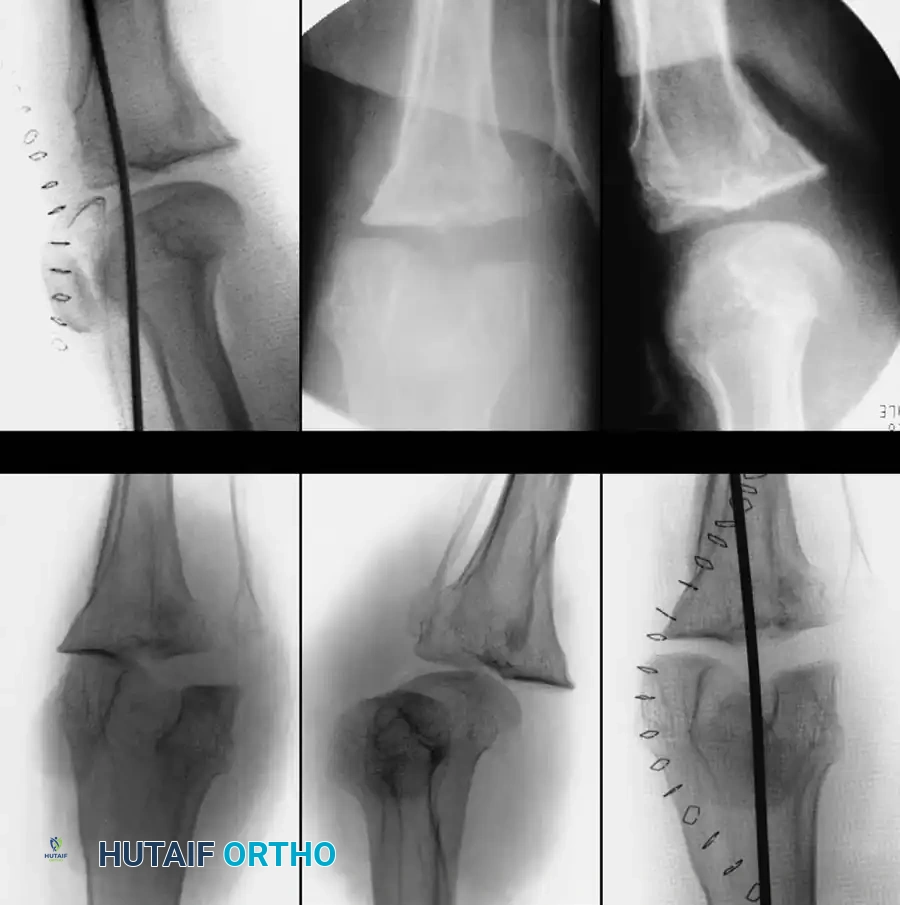

Fig. 58-2: Seventeen-year-old girl with a history of neurofibromatosis and a 6-week history of acute knee dislocation and inability to walk. (A and B) Anteroposterior and lateral radiographs of the knee showing posteromedial dislocation of the tibia with medial dislocation of the patella. (C and D) Anteroposterior and lateral radiographs at the time of open reduction and internal fixation utilizing a smooth Steinmann pin driven through the quadriceps mechanism, femur, and tibia to maintain temporary alignment. (E and F) Postoperative anteroposterior and lateral radiographs demonstrating mild persistent lateral subluxation but an overall good reduction of the knee and patellar dislocation.

- Incision: Utilize an extensile anteromedial approach to expose the knee joint. If the patella has been chronically displaced either medially or laterally (as seen in Fig. 58-2), the skin incision must be modified to correspond with the normal anatomical location of the medial borders of the quadriceps tendon, patella, and patellar tendon to allow for proper realignment of the extensor mechanism.

- Temporary Fixation: Due to the complete incompetence of the cruciate and collateral ligaments, the reduced joint will be grossly unstable. Temporary transarticular fixation is often required. As demonstrated in Figure 58-2, a heavy, smooth Steinmann pin can be driven antegrade through the quadriceps mechanism and distal femur, across the joint line, and into the proximal tibia to hold the reduction.